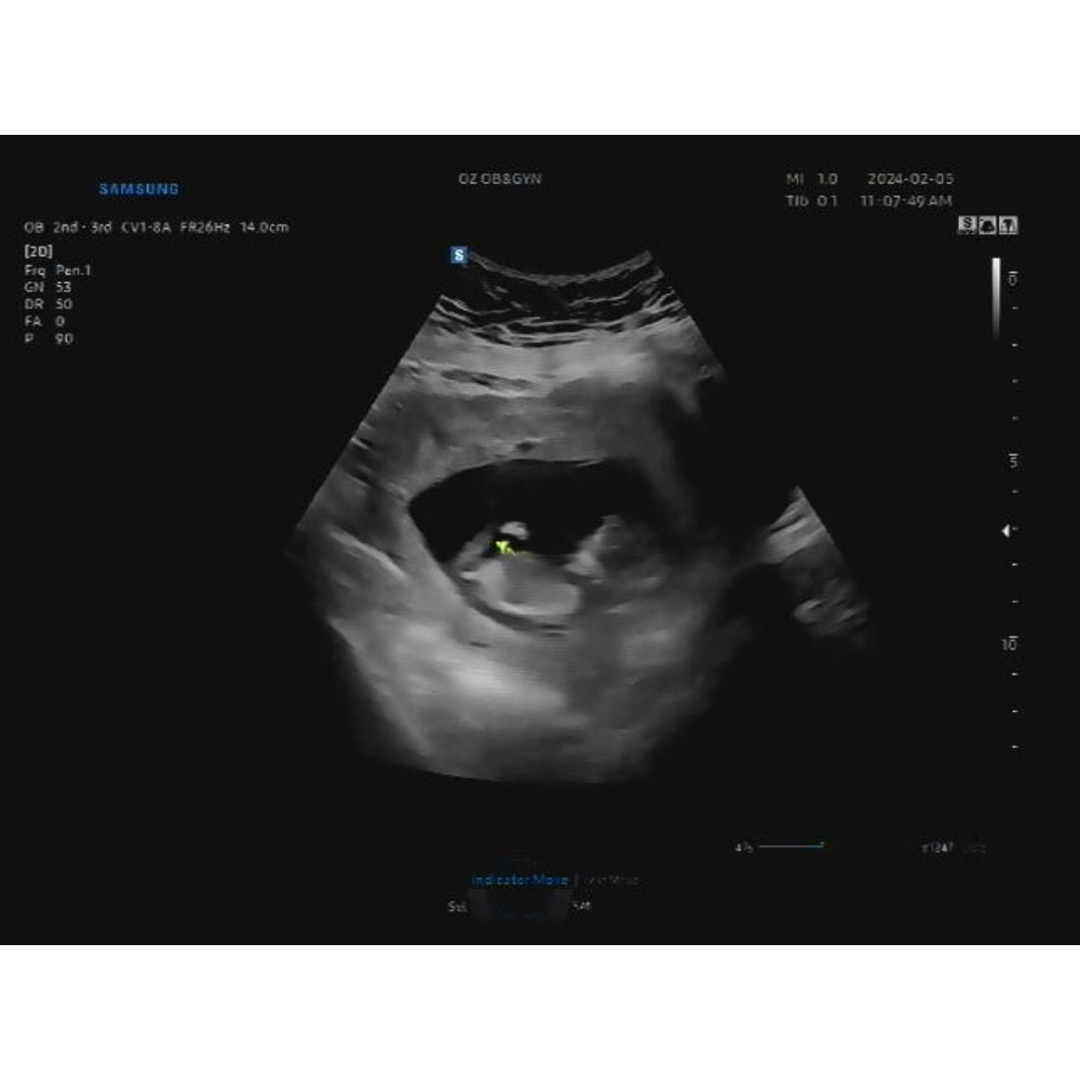

첫째때보다 더 떨리는 성별이네요.. 11주6일인데 한달 뒤에 보자고 하셔서 한달을 어떻게 참죠.. 각도법 열심히 봤는데 전 아직도 모르겠네요🤣🤣